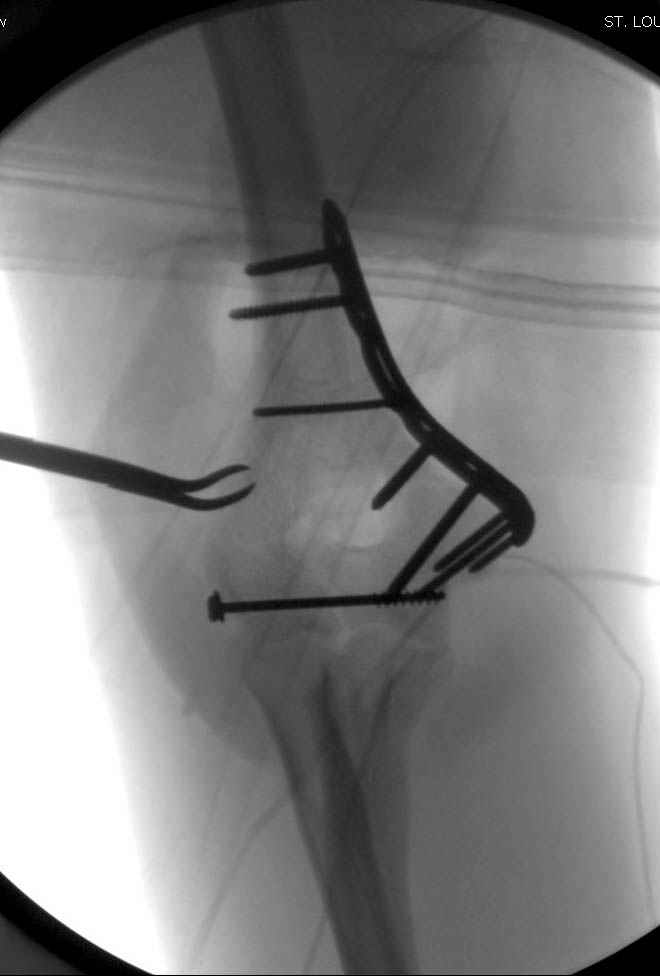

На шестой день сделали открытую репозицию чрезлоктевым доступом двумя locking plate, локтевой нерв был ушибленным, после операции положительная динамика в Flexor Carpi Ulnaris. Фиксацию локтевого отростка произвели tension band technique с дополнительным шурупом.

Этапы операции на снимках....